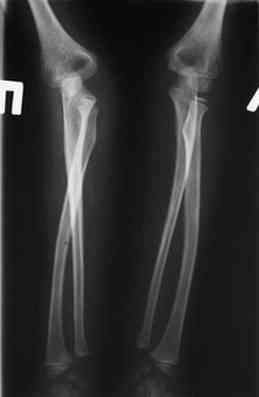

own> Мальчик 10 лет, из отдаленного района, 3 года назад...

оперировали подобный случай около 6 мес назад. Отличие только в одном-

давность травмы была до 2х лет.

2 По снятии аппарата через 2 мес после операции рефрактура в месте

остеотомии(на фоне активного ротационного движения)- под контролем ЭОП выполнен

интрамедуллярный остеосинтез TEN. Положение головки луча стабильное.